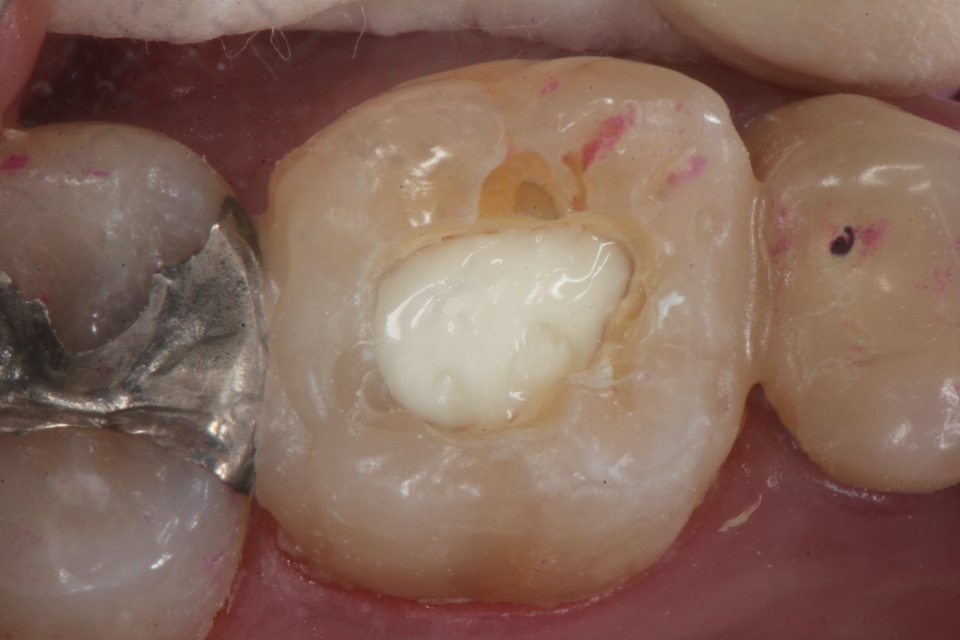

残根上のCR(ダイレクトボンディング)8 2025.11.12

ブリッジ脱離で2次カリエス+Perでグラグ… 2025.11.01

ブリッジ脱離で2次カリエス+Perでグラグ… 2025.10.31